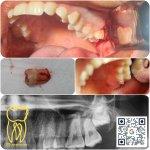

گالری